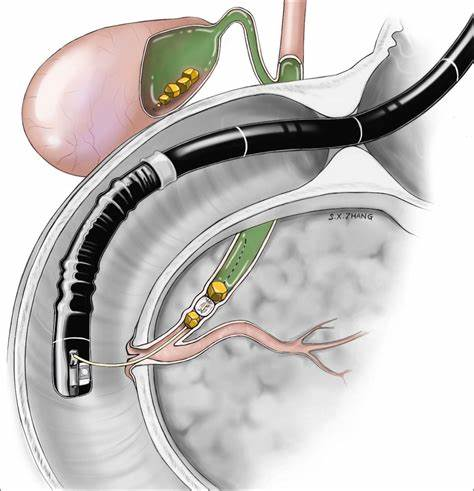

Advanced imaging

EUS-Guided Cholecystogastrostomy & Choledochoduodenostomy

EUS-guided biliary and gallbladder drainage procedures are advanced alternatives for patients in whom conventional ERCP is not feasible. These minimally invasive techniques provide internal drainage without the need for surgery or external tubes.

EUS-guided cholecystogastrostomy involves creating a connection between the gallbladder and stomach using a lumen-apposing metal stent (LAMS). It is especially beneficial for high-risk surgical patients with acute cholecystitis.

EUS-guided choledochoduodenostomy establishes drainage between the bile duct and duodenum, providing effective relief from biliary obstruction due to stones or malignancy.

These procedures offer rapid symptom relief, lower complication rates, and improved patient comfort compared to percutaneous drainage. They represent cutting-edge endoscopic care for complex biliary disorders.